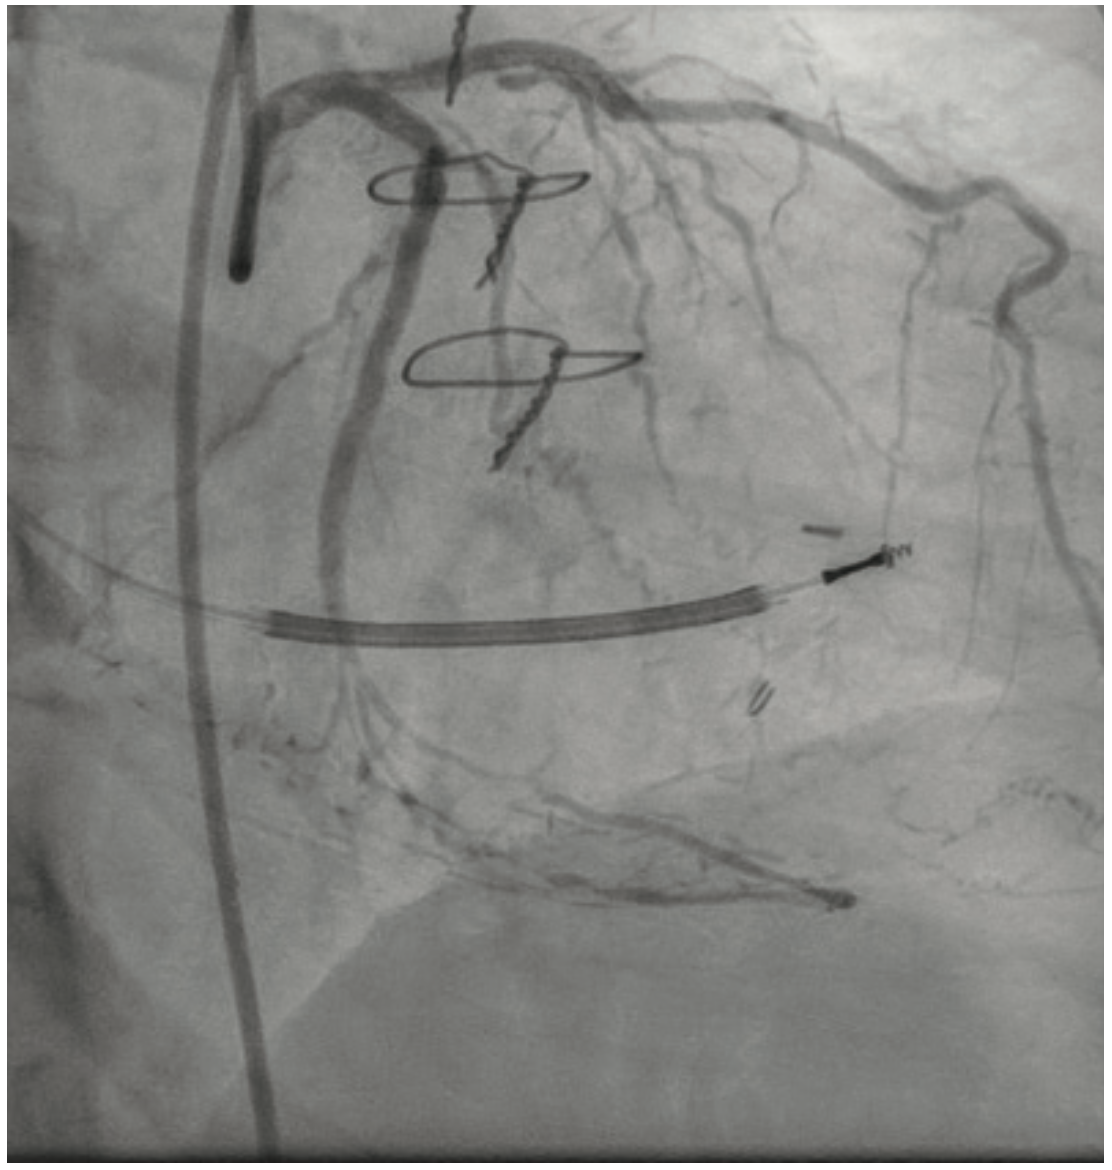

A Takeru 1.5 mm x 6 mm PTCA balloon was subsequently easily able to cross into the distal vessel and dilate the lesion with multiple inflations (Figure 6). After further predilation with larger PTCA balloons, technical success was achieved after successful placement of two Orsiro Mission drug-eluting stents (Biotronik) (Figure 7).

The patient was discharged the following day completely angina free and with a subjective increase in her LVEF on echocardiography to 40%-45%. She remained angina free at 15-day outpatient follow-up.